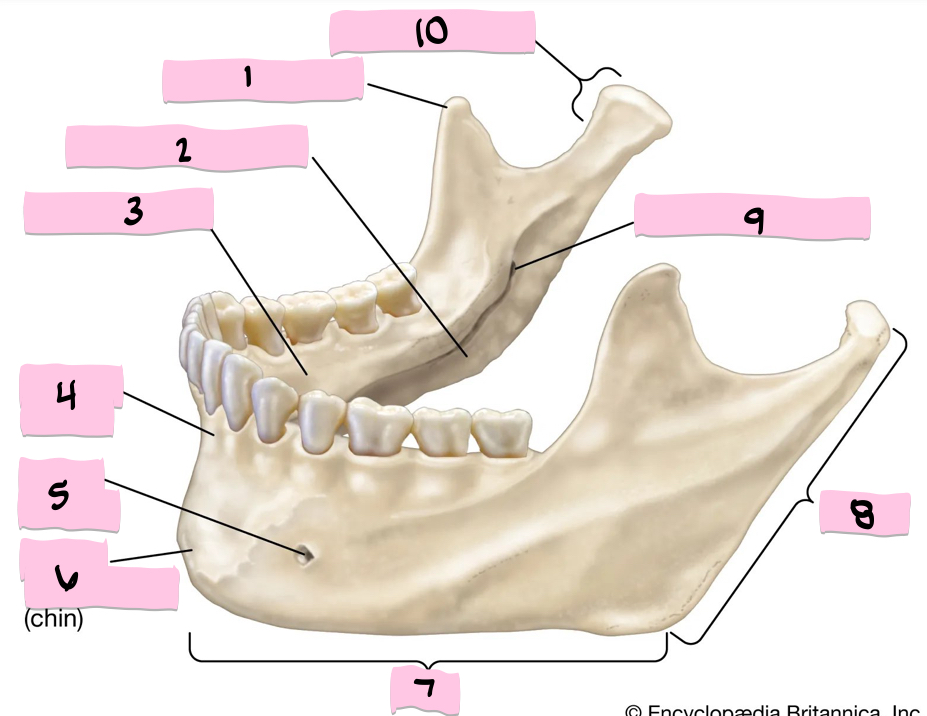

What is 1 pointing to?

Mentum

What is 2 pointing to?

Coranoid process

What is 3 pointing to?

Mandibular notch

What is 4 pointing to?

Condyloid process

What is 5 pointing to?

Ramus

What is 6 pointing to?

Body